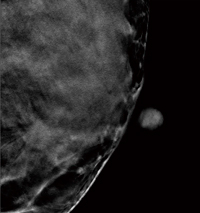

■症例1:spiculated massの検出

症例1:2D画像(所見部分拡大) |

症例1:トモシンセシス静止画像 |

症例1:左CCの2D画像 |

症例1:左CCのトモシンセシス静止画像(19スライス目) |